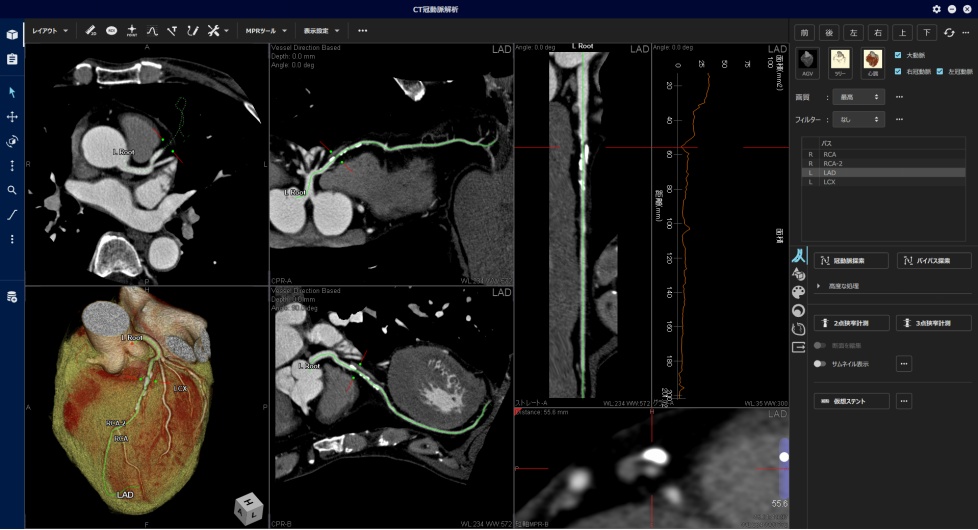

中外医学社 | 書籍詳細。臨床心臓CT学-基礎と実践マネージメント | 小山 靖史, 鈴木 諭。アプリケーション(心臓領域) | REVORAS。【N☆】令和6年(新米)コシヒカリ1等米10キロ。CT検査 | 戸畑共立病院。オプション検査 | 人間ドック健診センター | 大田区蒲田 牧田。。桜橋渡辺未来医療病院 MDCT検査予約。医学出版_循環器ナーシング16年6月号。CT検査 | 戸畑共立病院。心臓特化型画像診断センター「心臓画像クリニック(CVIC)飯田橋。朝倉書店『内科学』(第12版)デジタル付録。メジカルビュー社|診療放射線技師|心臓CT活用マニュアル。心臓Ⅰ:Step and shoot technique 岩城 卓(横浜栄共済病院。「臨床心臓CT学 基礎と実践マネージメント」小山 靖史定価: 22000円 (20000円+税)ぼぼ未使用でパラパラと見ただけで、状態はよいと思われます。書き込みも見返しましたがありませんでした(万が一あったら申し訳ございません)。表面に多少のスレやキズはあります。また天面に名前の印鑑がありマジックで消しています。あくまで写真のものをお渡しということでよろしくお願い致します。ご質問や価格交渉ありましたらメッセージくださいm(._.)m循環器内科、内科、カテ、カテーテル、CAG、PCI、FFRインターベンション、読影、放射線冠動脈、動脈硬化冠動脈疾患、虚血性心疾患、狭心症、心筋梗塞高血圧、糖尿病、脂質異常症、肥満